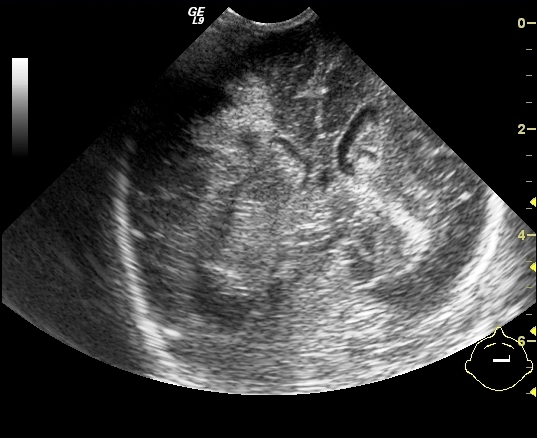

Necrotizing enterocolitis (NEC). It is a severe intestinal necrotizing disease of the newborns. It usually occurs as early as the first 10 days of life, but can happen in the first few months after birth. Vomiting, distended intestines, bloody stool, acidosis, peritonitis and perforation are frequent findings. Plain abdominal X-ray can be non-informative in the early stages of the disease; later distension indicates the separation of loops due to wall thickening. Often, air bubbles appear in the intestinal subserosal or submocosal layers, as characteristic signs of “intestinal pneumatosis”. The intramural air can diffuse to the mesenteric veins and appear in the portal circulation in the projection of the liver. Free abdominal air is indicative of perforation and requires surgical intervention. US examination can reveal these characteristics of the disease before X-ray is indicative. US can depict thickened intestinal wall, portal and intramural air, abdominal free fluid or abscesses.

19. Distended bowel loops. Air is seen in the intestinal wall, intestinal pneumatosis. Necrotizing enterocolitis.

20. NEC, US examination. Free abdominal fluid, with dense inner echos. Air bullbles in the intestinal wall: “zebra” sign (arrow).